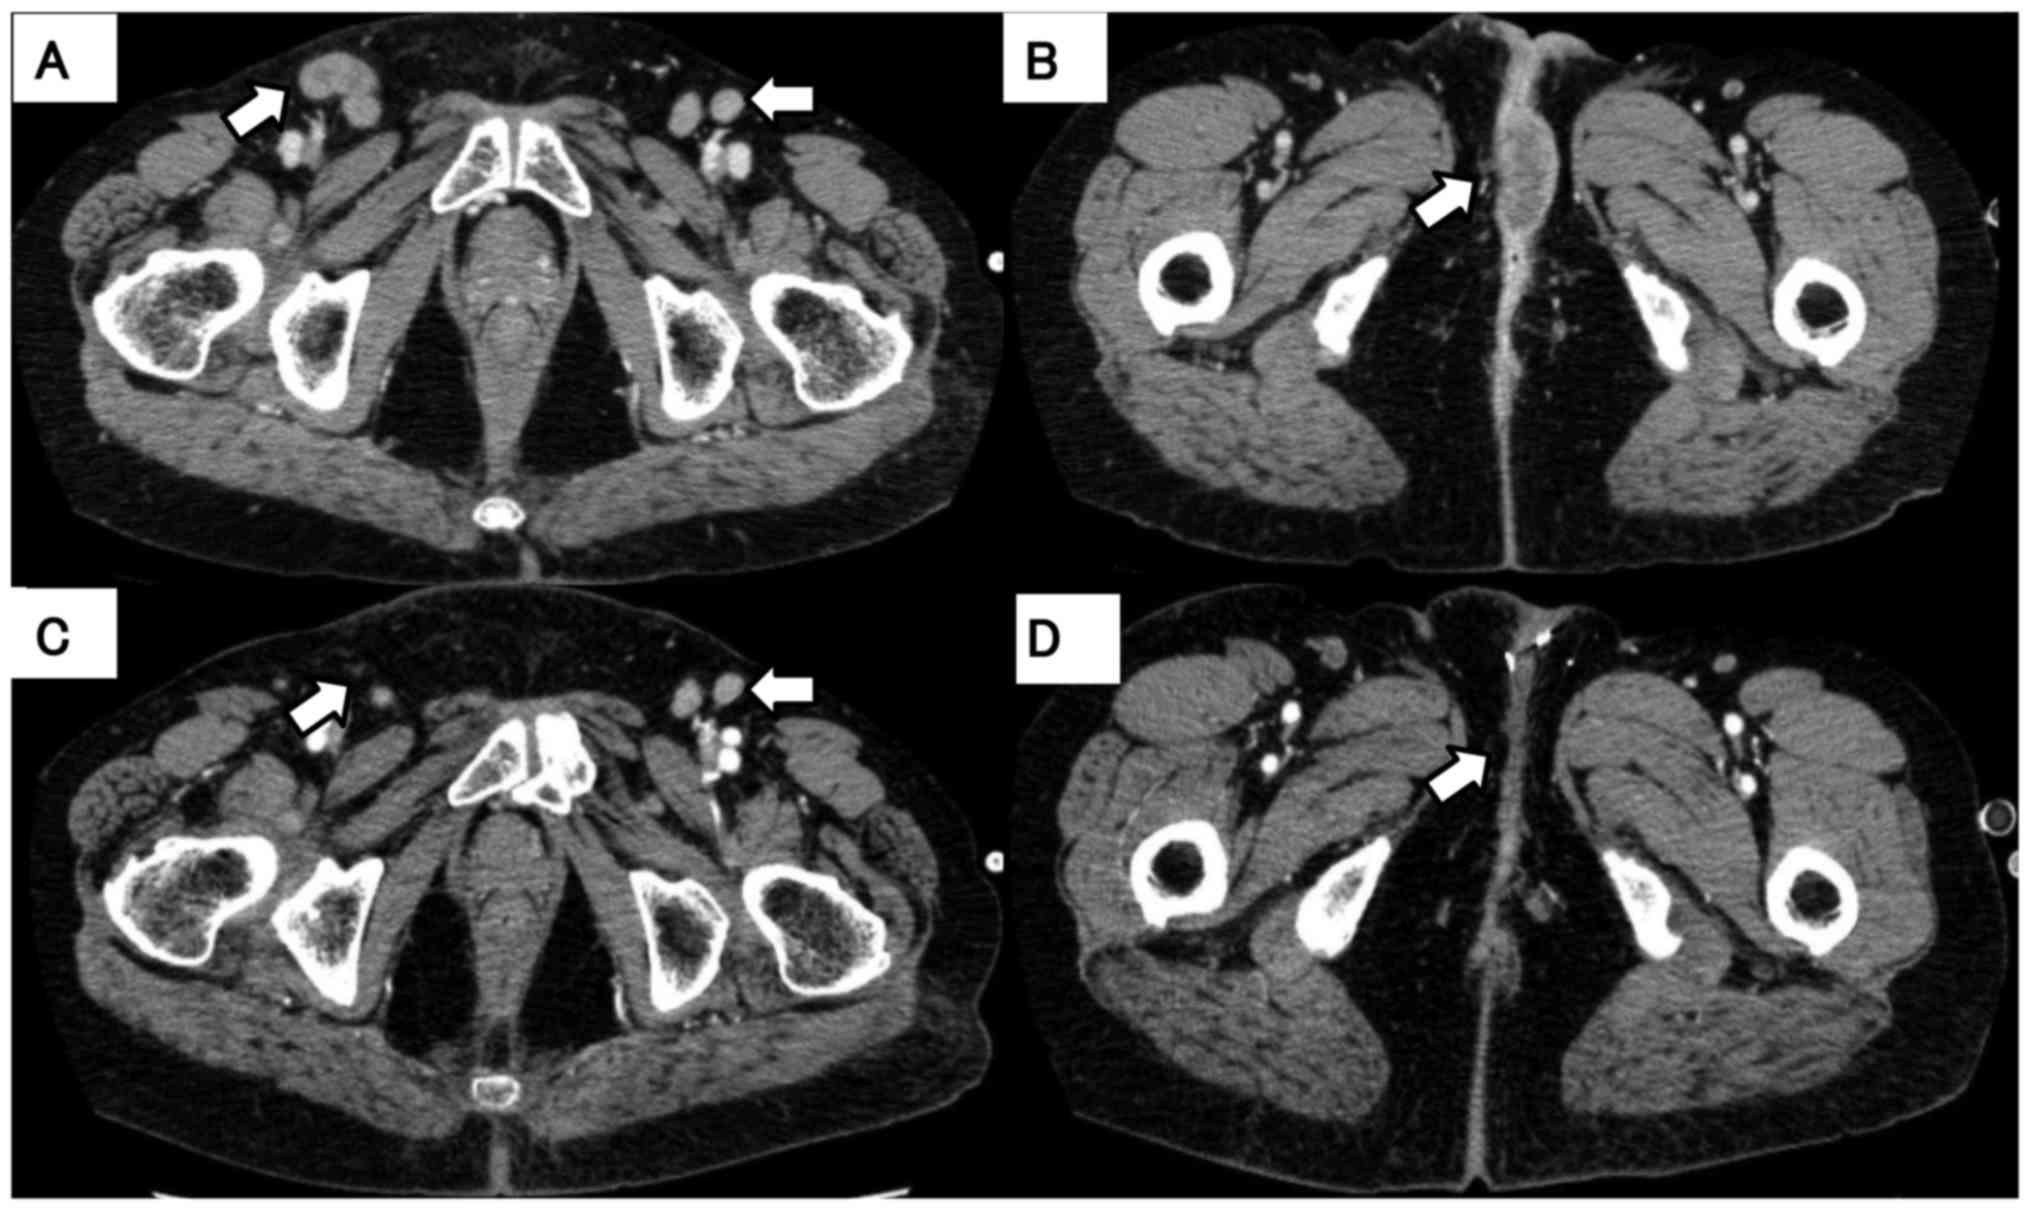

A 58-year-old woman was referred to the Shinshu University Hospital (Matsumoto, Japan) in August 2014 to receive further treatment for previously diagnosed EMPD. The findings of the physical examinations of the chest and abdomen were unremarkable, but a giant, slightly raised, erythematous and hemorrhagic granular lesion in the perineum and a mass on the inner thigh were identified (Fig. 1). Lower abdominal computed tomography (CT) revealed enlargement of the inguinal lesions, the mass in the perineum, and within the vagina (Fig. 2, arrows). The disease was initially diagnosed 12 years prior and the patient had undergone simple vulvectomy. The histological and immunohistochemical findings are presented in Fig. 3. However, the disease relapsed locally within the subsequent 4 years and the patient underwent vulvectomy twice and cystostomy. In addition, episioplasty was performed for incontinence as a postoperative complication. Two years after the last operation, the disease relapsed with a tumor measuring 4 cm. The patient refused further surgical treatment and was followed up. Four years later, the tumors had increased in size and the patient experienced pain and difficulty walking; she was then referred to our hospital to receive chemotherapy or alternative therapy. The patient had a history of breast cancer prior to the development of EMPD, which was completely resected, and has been followed up without any signs of relapse. Biopsy of the vulval lesion was performed and the pathological findings confirmed EMPD (Fig. 4A). Immunohistochemical analysis revealed that tumor cells were positive for HER2 and cytokeratin (CK) 7, and were negative for estrogen and progesterone receptors (Fig. 4B-E).

The patient was treated with trastuzumab plus paclitaxel. Trastuzumab was administered at a loading dose of 4 mg/kg followed by 2 mg/kg weekly in combination with weekly paclitaxel at 80 mg/m2. No adverse effects, such as cardiotoxicity, neurotoxicity, or hematotoxicity, have been observed to date. The tumors decreased in size and the inguinal lymph nodes disappeared 6 months after the initiation of chemotherapy (Fig. 2C and D). This treatment has been continued for 2 years and 6 months, with partial response and good control of the clinical condition.